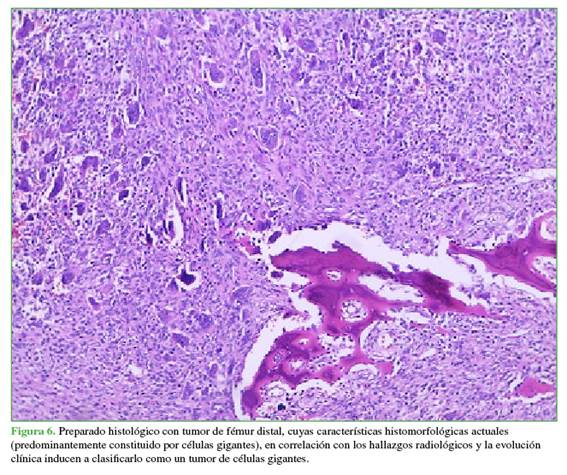

El estudio de anatomía patológica informó que los cortes mostraron un tumor constituido predominantemente por numerosas células gigantes multinucleadas de tipo osteoclásticas entremezcladas en sectores con células fusadas mononucleares. Se reconoció un foco de proliferación fusocelular de disposición verticilada, en el cual se distinguieron macrófagos de apariencia espumosa (Figura 6).

En los preparados histológicos, se debe tener en cuenta la clasificación de  Campanacci:

I: Radiología e histología con baja agresividad.

II: Radiología con agresividad y con periostio intacto. Histología benigna.

III:       Crecimiento agresivo y masa de tejidos blandos tanto en los estudios radiológicos como en la histología. Los diagnósticos diferenciales más frecuentes son: condroblastoma (Figura 8), quiste óseo aneurismático (Figura 9) y osteosarcoma de tipo telangiectásico.